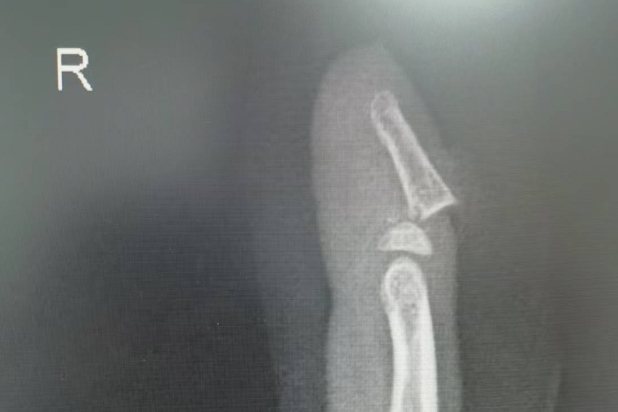

手指被门夹伤,严重时可能导致骨折甚至指甲外翻。

桡骨远端骨折,通过手法复位